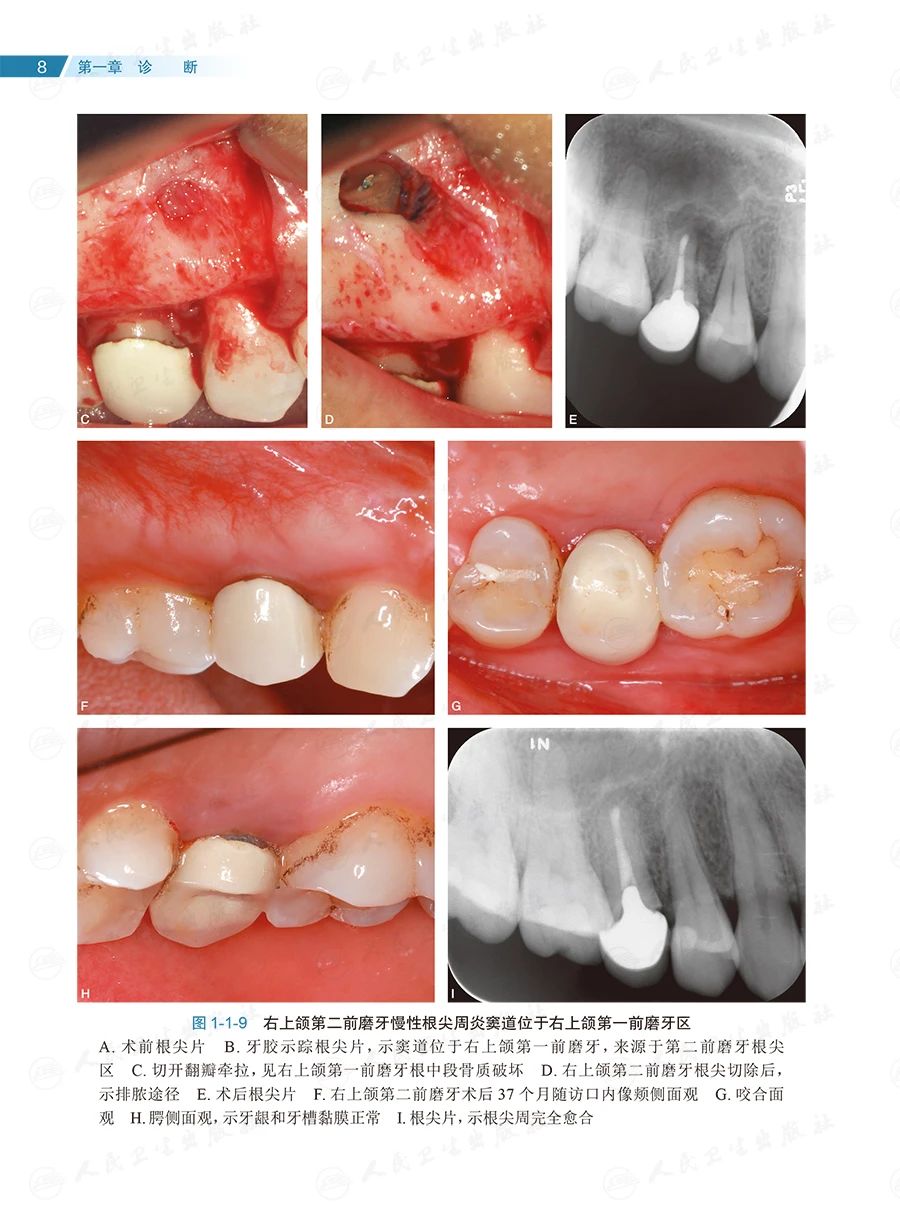

全书共133个临床病例、约1400幅照片,内容全面、图文并茂、形象直观。按照诊断、确定治疗方案和治疗的顺序,全书分为六章:第一章为诊断,主要讨论根尖周透射影、根裂的诊断和鉴别诊断;第二章为治疗方案选择,重点探讨非手术和手术(再)治疗方案的选择;第三章为在体手术治疗,即显微根尖外科,讨论特定牙位和牙根的手术,以及一些复杂疑难牙髓病、根尖周病的手术治疗;第四章为离体手术治疗,即显微意向再植术,全面讨论其适应证;第五章为多学科合作,包括牙髓源性上颌窦炎、联合应用引导性组织再生术(guided tissue regeneration,GTR)、自体牙移植术中的应用;第六章为全文总结,系统阐明牙髓病、根尖周病治疗的整体策略。